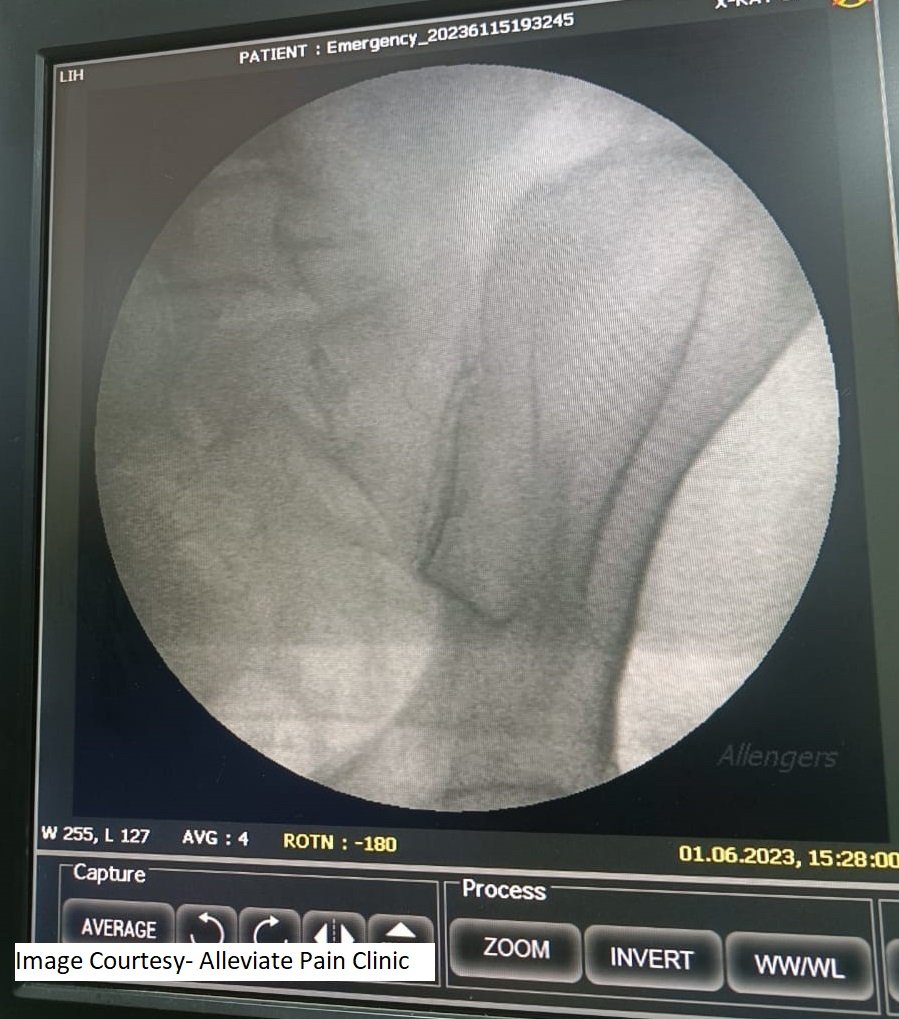

Fluoroscopy Guidance

Fluoroscopy is a real-time X-ray technique that allows the physician to visualize the SI joint and surrounding structures with precision. This helps guide the needle placement accurately.

A local anesthetic is administered to numb the skin and underlying tissue. Then, a thin, specialized needle is inserted into the SI joint, and contrast dye is injected to confirm the needle’s position. Once the correct placement is confirmed, a mixture of a corticosteroid and anesthetic is injected into the joint to reduce inflammation and alleviate pain.

Fluoroscopic guided Sacroiliac joint injection. Needle position confirmed by dye spread.However, the clinic’s approach didn’t stop at the injection. Prerna was also provided with a structured physiotherapy program to strengthen her core muscles and improve her overall spinal stability. This holistic approach addressed the root cause of her pain and provided her with the tools to maintain her improved quality of life.